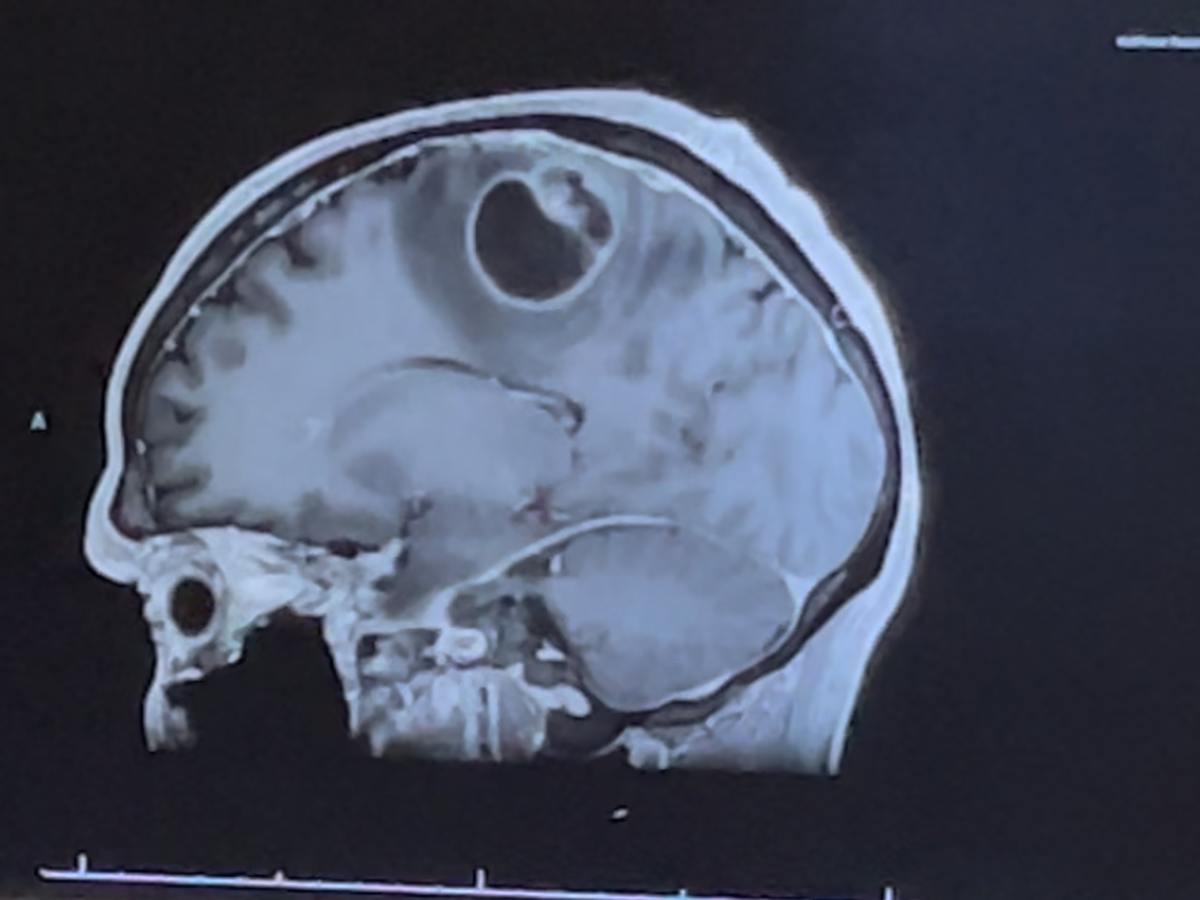

On March 27, 2025, I took my dad to St. Mary’s Hospital after he suddenly lost function on the right side of his body. After undergoing CT scans and an MRI, doctors discovered a 3.6 cm mass on the left side of his brain—the area responsible for controlling the right side of the body.